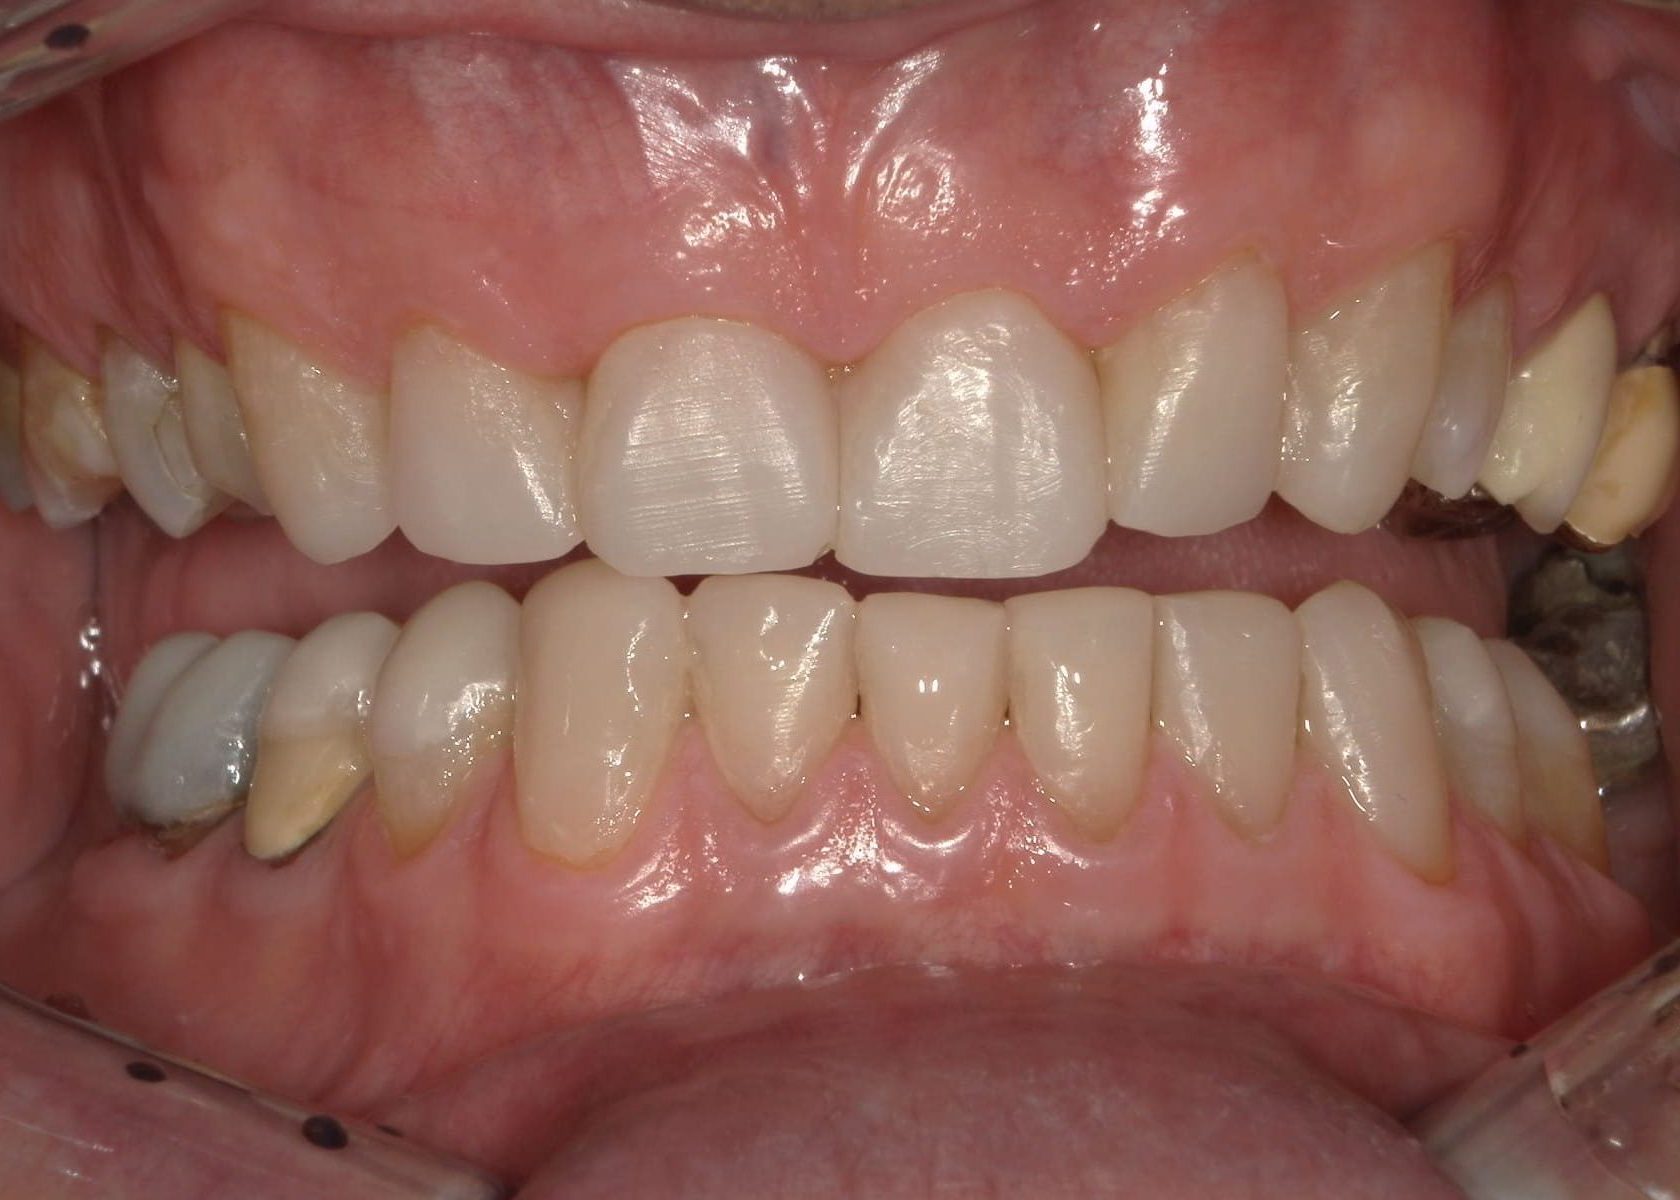

Prima

Dopo